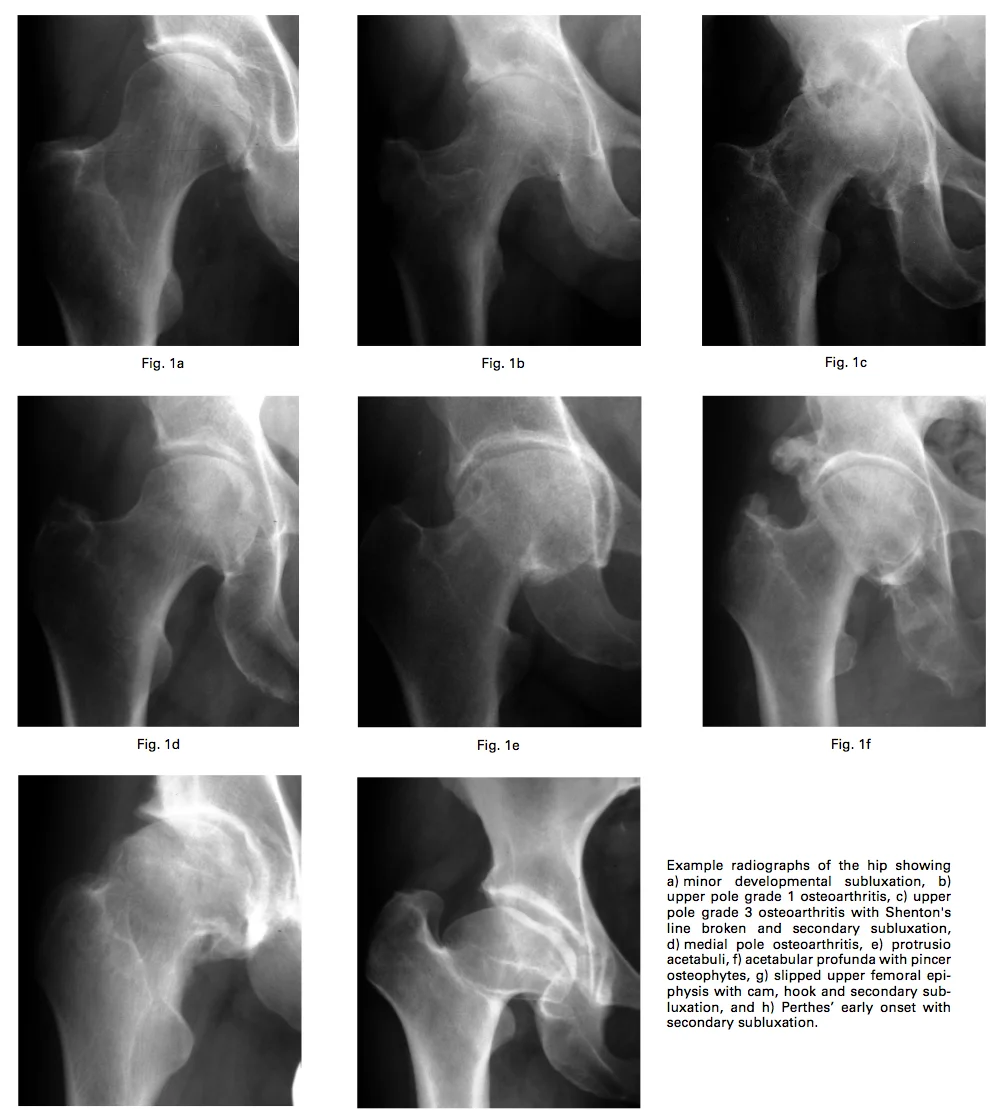

Causas menos óbvias são alterações do formato do quadril que levam a forças anormais atuando sobre uma cartilagem normal; por exemplo: displasia de quadril, impacto femoroacetabular, lega-perthes-calvé, profusão acetabular, epifisiólise (deslizamento epifisário). Figura abaixo demonstra diversas alterações de formato associadas a artrose.

Legenda: diversos formatos de quadril que levam a artrose. Hamilton, H W, and J Jamieson. 2012. “The Classification of Degenerative Hip Disease..” The Journal of bone and joint surgery. British volume 94(9): 1193–1201.